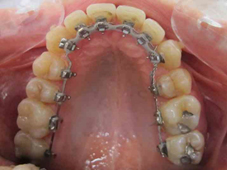

Arcade maxillaire avant traitement orthodontique, séquelles de maladie parodontale

Après traitement orthodontique et réalisation d’une attelle coulée collée (courtoisie Dr Patrick Fournier)